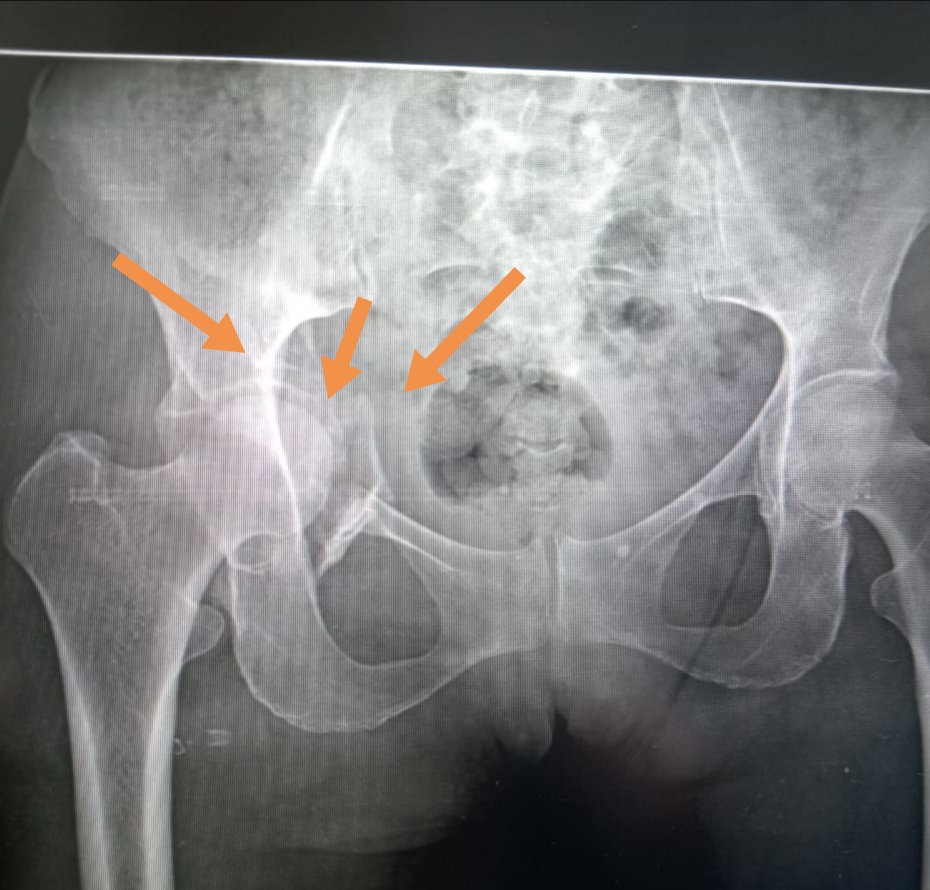

قام الفريق الطبي بقسم جراحة العظام بمستشفى أبو حماد المركزي، بقيادة الدكتور محمد منصور العش استشاري العظام والحاصل علي دكتوراة في جراحات الحوض وعضو وحدة كسور الحوض بمستشفي الهرم التخصصي، ومشاركة الدكتور محمود موسي أبوهاشم رئيس قسم العظام بالمستشفى، والدكتور أيمن عبدالصمد طبيب زمالة العظام، والدكتور عبدالرحمن الحفناوي، والدكتور محمد رفعت، والدكتور حاتم ثروت أطباء العظام، والدكتور عماد محمود سامي استشاري التخدير، تحت إشراف الدكتور محمد عبدالهادي حموده مدير المستشفى، بإجراء عملية تثبيت لكسر بالحوض بالحق الحرقفي الأمامي مع خلع مركزي بمفصل الفخذ لمريضة تبلغ من العمر ٥٠ عاماً، محولة من إحدى مستشفيات المحافظة، كانت تعاني من كسر بالحق الحرقفي وخلع بمفصل الفخذ، وبعد إجراء كافة الفحوصات الطبية والأشعات اللازمة للمريضة، وإعداد خطة علاجية متكاملة من قبل الفريق الطبي واستكمال عروضات المسالك البولية والجراحة، تم رد الخلع وتثبيت الكسر بواسطة شريحة ومسامير، والحالة الآن مستقرة وتتلقى الرعاية الطبية تحت إشراف الأطباء بقسم العظام بالمستشفى.

وأشار محمود عبدالفتاح مدير المكتب الإعلامي بالمديرية، الى أن هذه العملية تعد ذات طابع خاص، والذي يتميز به قسم جراحة العظام بمستشفى أبوحماد المركزي، مضيفاً بأن القسم قام بإجراء ٥٠ عملية جراحية حتى الآن خلال الأشهر الماضية لتثبيت كسور بعظام الحوض والحق الحرقفي بالغة الصعوبة، لافتاً أن الدكتور هاني جميعة قدم الشكر للدكتور شريف شاهين مدير عام الطب العلاجي، ولمدير المستشفى، وللسادة الأطباء، وهيئة التمريض، وفنيين الأشعة، والفريق المعاون، علي الجهود المبذولة لصالح المرضى بمحافظة الشرقية...